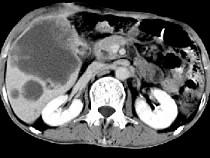

问题 男,49岁,右上腹痛半年,轻度黄疸,AFP阴性,CT检查如图,最可能的诊断为()

选项 A.原发性肝癌 B.胆管细胞癌 C.局灶性脂肪肝 D.肝脓肿 E.肝淋巴管瘤

答案 B